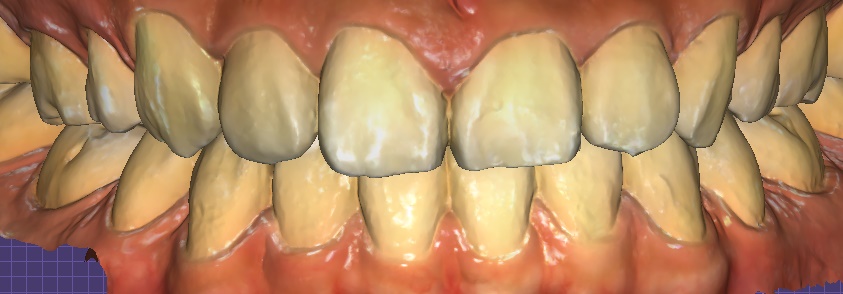

① 디지털 스캔 & 디자인

– 구강스캐너로 정밀한 데이터 채득 → 3D 디자인 및 시뮬레이션

오브제로 라미네이트 시뮬레이션